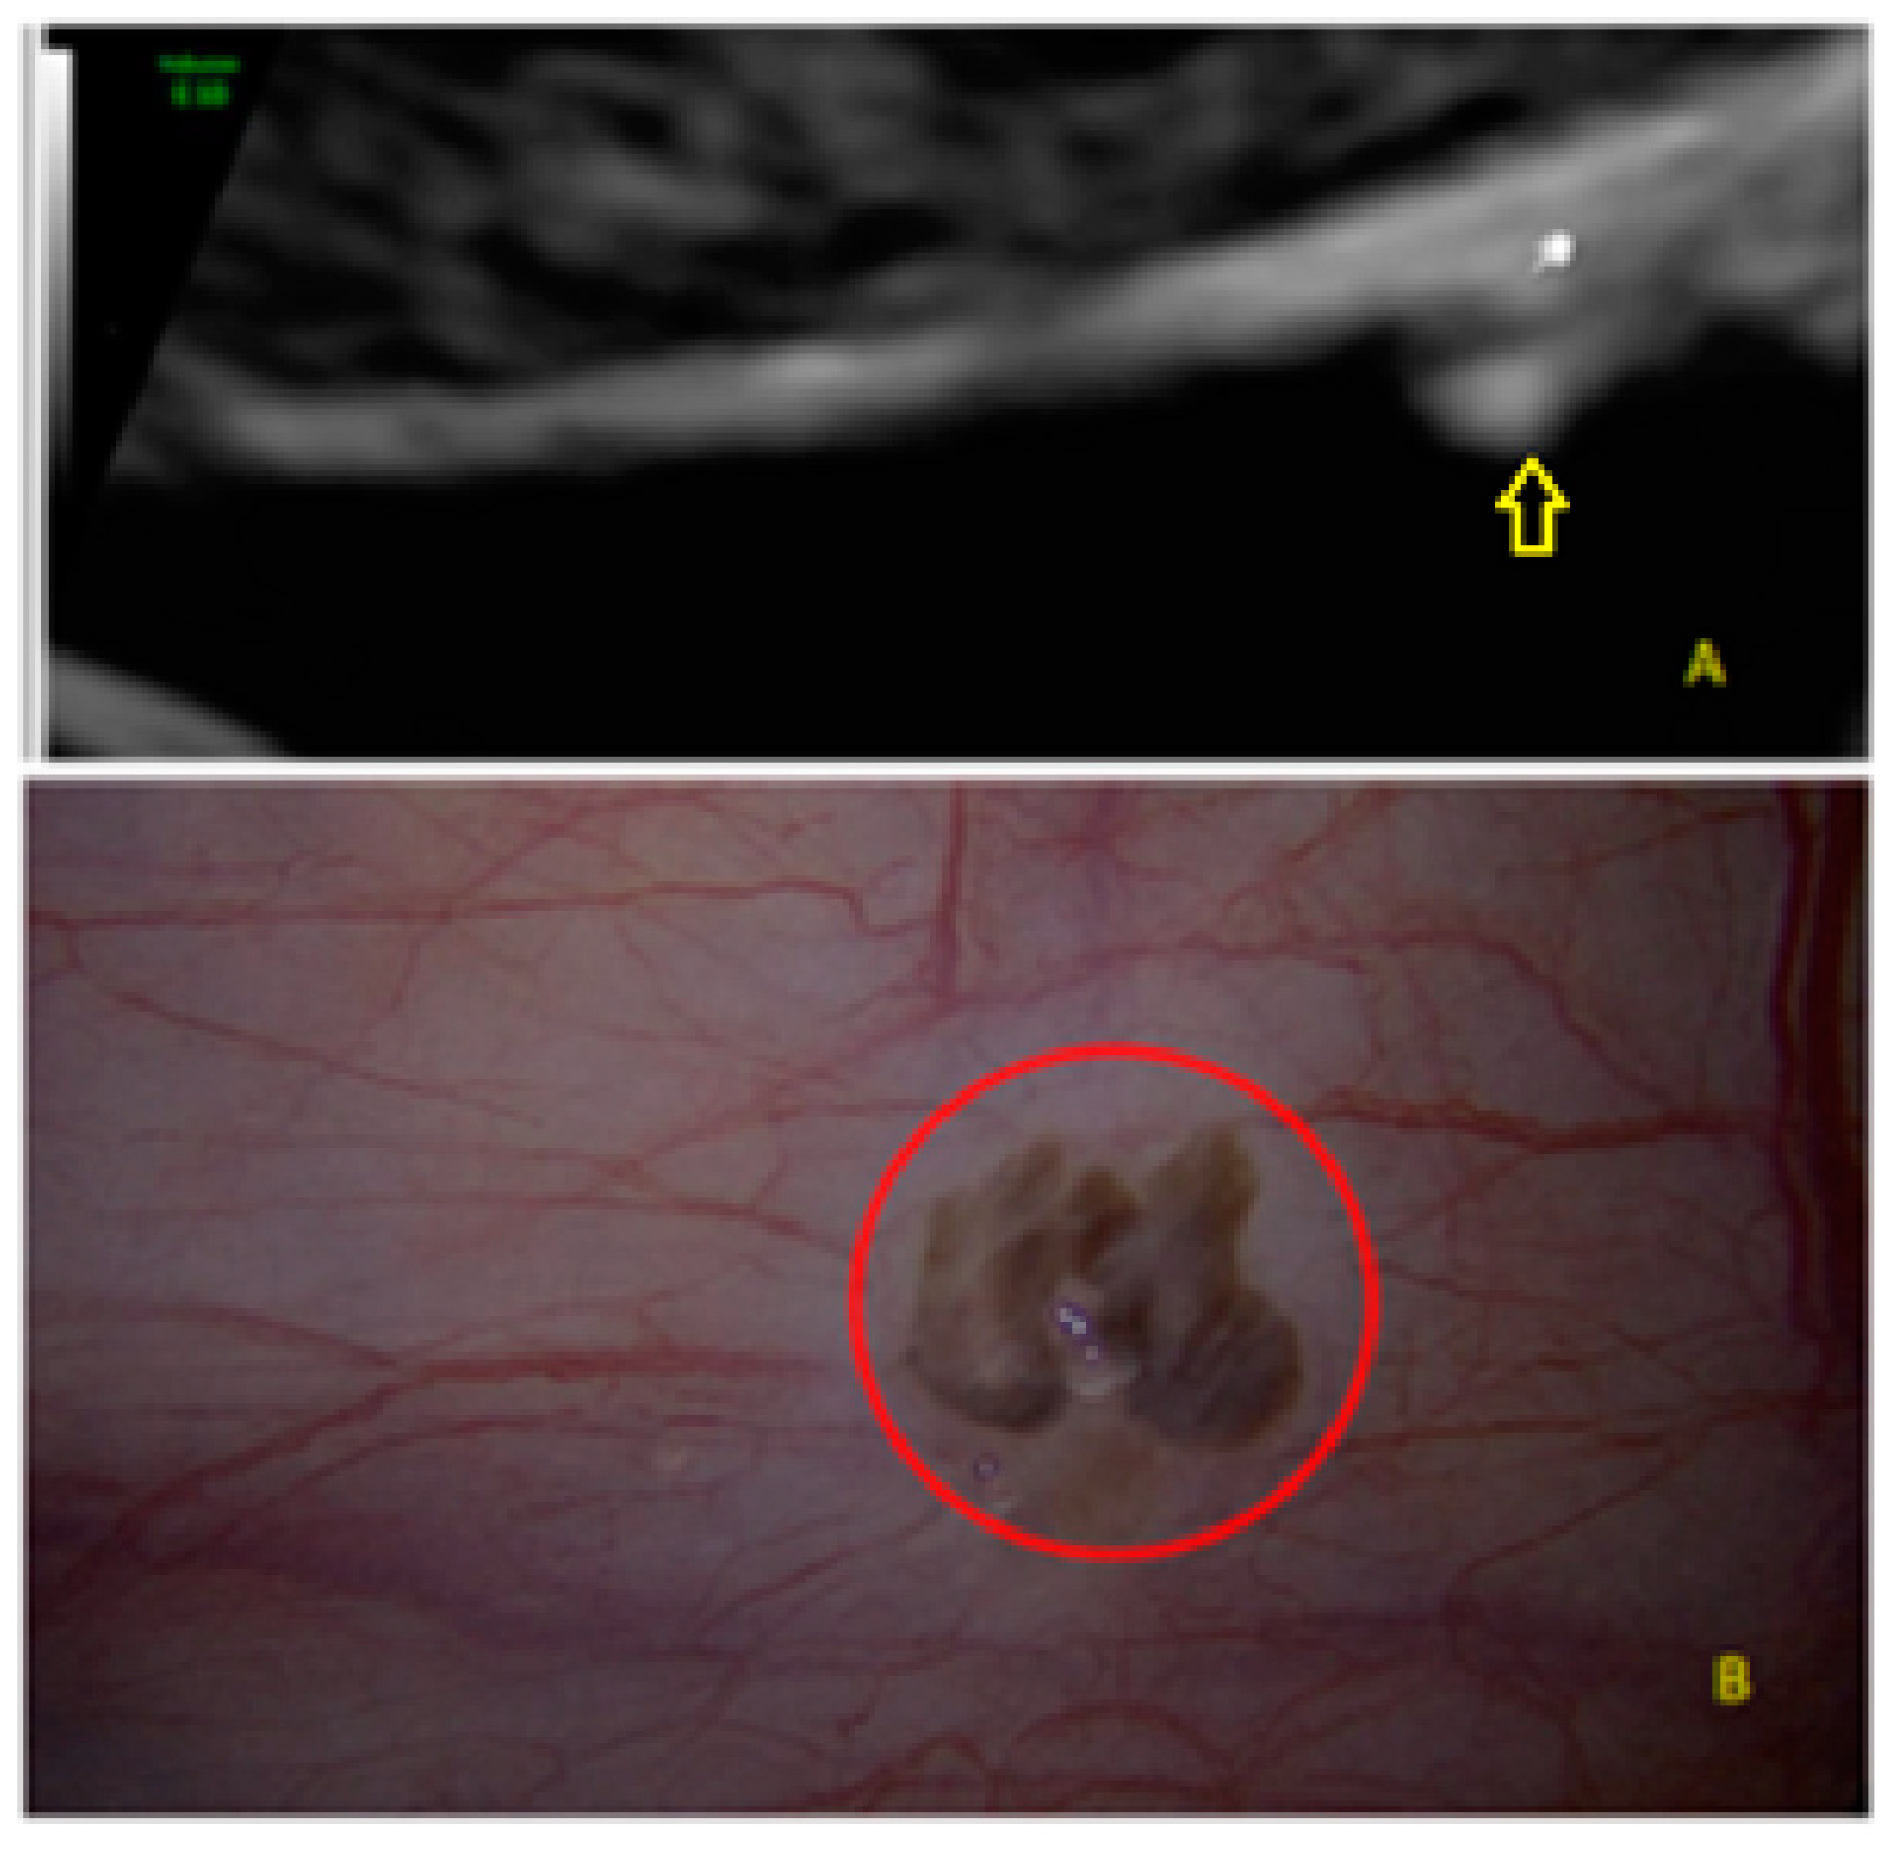

- The presence of hypoechogenic associated tissue (hypoechoic areas surrounding a small cyst area; we called this a “hat”). This tissue does not protrude or invaginate the peritoneal surface.

- The lesion may be convex, protruding from the peritoneal surface into the peritoneal cavity (we called this “bulging”), or it may appear as a concave defect in the peritoneum (we called this a “pocket”).

- The presence of hyperechoic foci (we called this a “pearl”).